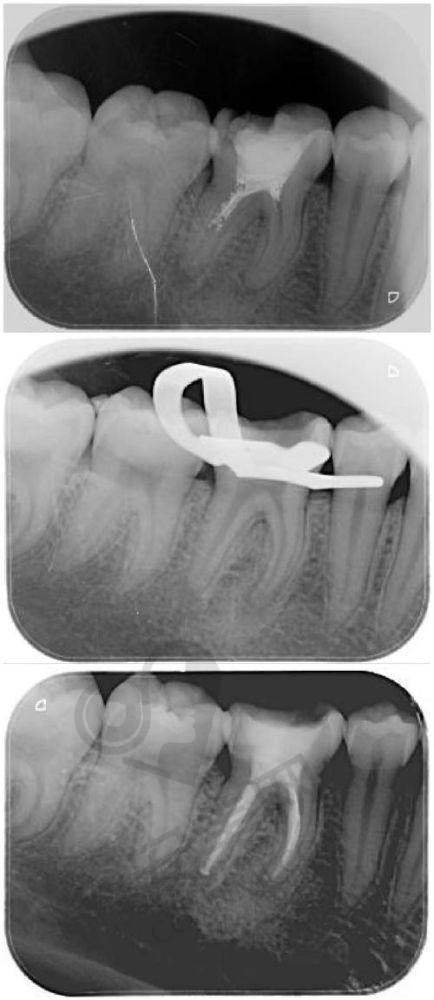

我来到医院后,首先是前台的工作人员热情地接待了我,帮我安排了医生。医生先是详细地询问了我的牙齿疼痛情况,比如疼痛的时间、程度、是否有冷热刺激痛等。然后让我躺在治疗椅上,用专精的口腔检查工具对我的牙齿进行了仔细的检查。接着,为了更正确地了解牙齿内部的情况,医生安排我去拍了牙片。牙片可以清晰地显示牙齿的根管形态、炎症范围等。通过这些检查,医生正确地判断出了我哪颗牙齿需要进行根管治疗,以及制定了详细的治疗方案。

第二次就诊的时候,医生要对根管进行预备。这一步主要是清理根管内的感染物质,扩大根管,为下一步的充填做准备。医生先用根管锉等工具对根管进行清理和塑形。在这个过程中,虽然打了麻药,但还是会有一些轻微的感觉,不过完全可以忍受。医生的操作特别轻柔,而且会时不时地询问我的感受。整个根管预备过程大概持续了一个多小时。结束后,医生在根管里封了药,让药物进一步杀灭根管内的细菌。

经过几次封药后,牙齿没有明显的不适症状,医生就开始进行根管充填了。这是根管治疗的末尾一步,也是非常关键的一步。医生先用牙胶尖等材料将根管严密地充填起来,防止细菌再次进入。然后对牙齿的表面进行了修复,修复了牙齿的外形和功能。在充填和修复的过程中,也没有什么疼痛感。治疗结束后,医生还叮嘱了我一些注意事项,比如短期内不要用这颗牙齿咬太硬的东西等。

医院采用了精良的根管治疗技术,比如显微镜根管治疗。显微镜可以让医生更清晰地看到根管内部的情况,提高治疗的正确性和成功几率。而且医院的根管测量仪等设备也特别精良,能够严谨地测量根管的长度,确保治疗的成效。